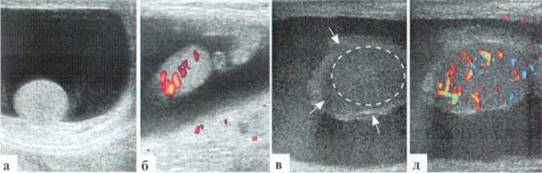

Трансформация гидатиды у детей является наиболее частой причиной развития СОМ. Причины возникновения этой патологии не всегда понятны, однозначного мнения о генезе заболевания в настоящий момент нет. Возможен как механический перекрут ножки гидатиды, так и ее инфаркт по невыясненным причинам. Гидатида значительно увеличивается в размерах, часто приобретает «ячеистую» структуру. Форма трансформированной гидатиды обычно округлая или овальная. Размеры чаще от 3x3 до 5x6 мм. При допплеровском исследовании трансформированная гидатита всегда аваскулярна (2.1.1).

Рис. 2.1.1. Трансформация гидатиды:

а — внешний вид пациента; б, в — гидатида (пунктир) у верхнего полюса яичка

В редких случаях диаметр измененной гидатиты может превышать 10—12 мм и у маленьких детей практически достигать размеров яичка (рис. 2.1.2).

Рис. 2.1.2. Крупные размеры трансформированной гидатиды: 1 — яичко, 2 — гидатида. Размеры яичка и гидатиды практически одинаковы. Сосудистый рисунок при ДДС в гидатиде не прослеживается (б)